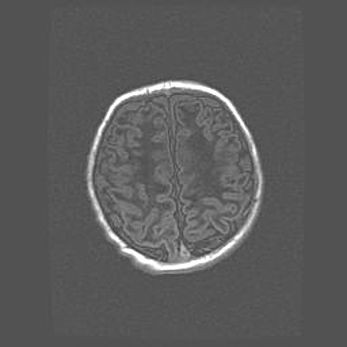

Церебральная ишемия II.

Возраст: 5 дней

Вес: 3400 г

Пол: женский

Окружность головы: 35 см

Срок гестации: 39 недель

Церебральная ишемия – это заболевание, характеризующееся недостаточностью (гипоксией) либо полным прекращением (аноксией) снабжения мозга кислородом по причине закупорки одного или нескольких сосудов. Это приводит к  что метаболическим расстройствам различной степени тяжести в тканях головного мозга, развитию коагуляционных некрозов и гибели нейронов.